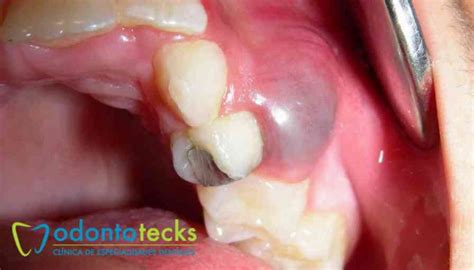

Clínicamente, como se mencionó, la mayoría son asintomáticos; a la palpación puede notarse una ligera expansión ósea indolora si la lesión es grande. En ocasiones el paciente presenta una fístula en la encía (un conducto de drenaje) o leve molestia crónica.

La identificación de un quiste radicular combina la evaluación clínica, pruebas de vitalidad y técnicas de imagen. En la exploración clínica, un diente asociado a un posible quiste radicular suele dar respuesta negativa a las pruebas de vitalidad pulpar, lo que confirma la necrosis o pérdida de función de la pulpa. Puede haber una historia de caries profunda, tratamiento endodóntico fallido o trauma previo en ese diente.

Al palpar, si el quiste es grande, podría notarse una expansión ósea dura e indolora en la zona; si está activo o infectado, podría palparse dolor o fluctuación (indicativa de contenido líquido). La radiografía periapical es la herramienta diagnóstica de primera línea: típicamente muestra una imagen radiolúcida redondeada u oval en el ápice radicular, con bordes bien delimitados y a menudo una fina cortical esclerosada periférica.